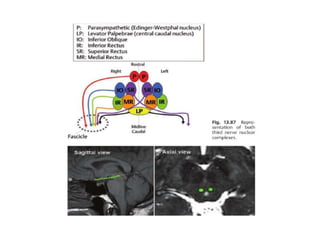

3rd n. anatomy

• Complex of subnuclei(dorsal of midbrain) –>subarachnoid space-

>sup. Cerebral a. and post. Cerebral a.-> cavernous sinus->sup.

orbital fissure, annulus of zinn->sup. division(levator, SR), inf.

Division(parasym,MR,IR,IO)

3rd n. anatomy •Complex of subnuclei(dorsal of midbrain) –>subarachnoid space- >sup. Cerebral a. and post. Cerebral a.-> cavernous sinus->sup. orbital fissure, annulus of zinn->sup. division(levator, SR), inf. Division(parasym,MR,IR,IO)